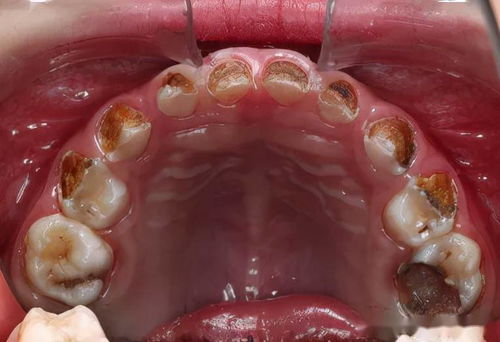

龋病的危害 龋病俗称虫牙、蛀牙,是细菌性疾病,可以继发牙髓炎和根尖周炎,甚至能引起牙槽骨和颌骨炎症。如不及时治疗,病变继续发展,形成龋洞,终至牙冠完全破坏消失,其发展的最终... 牙齿治疗 南光耀 2996 2024-03-25

龋病宜早治疗 龋病是人类的口腔常见病,发病率高,分布广,不论什么性别、年龄、地区、民族,均不能幸免,世界卫生组织已将龋病、癌症和心血管病并列为当代危害人类健康的三大疾病。龋病... 牙齿治疗 巨伟懋 557 2023-12-28

恒牙龋病的发病特点和影响 儿童龋病在临床上患病率较高,是最常见的儿童口腔疾病。其病因和组织病理的改变与成人恒牙龋无显著差异,但儿童处于生长发育阶段,乳牙和恒牙的牙体硬组织结构疏松,致使儿... 牙齿治疗 阙德厚 1258 2024-04-02

龋齿一定会牙疼吗 龋齿有一个发生、发展过程,由浅逐渐变深。患龋齿在开始时是不会感到疼痛的。龋齿发展到接近牙时才会引起疼痛,但往往是在遇冷热酸甜刺激后引起疼痛。龋齿发展引起牙髓炎时... 牙齿治疗 彤依波 851 2024-03-28